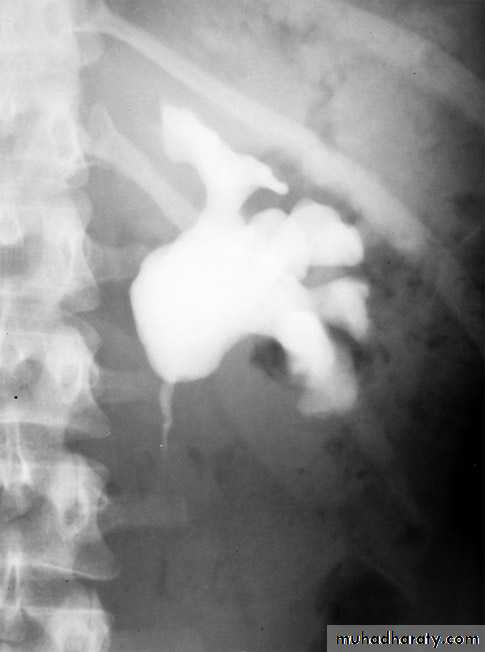

Ureterocele :

Congenital cystic dilatation of lower end of ureter ( intra-mural part) due to pin-hole meatus . May be simple or ectopic .

IVU :

- There is rounded or elliptical dilatation of lower end of ureter with thin lineal filling defect around it , resembling (cobra head appearance),

- Proximal dilatation of rest of ureter .

- In advanced cases hydronephrosis .

- In obstructed ureterocele , filling defect in the bladder